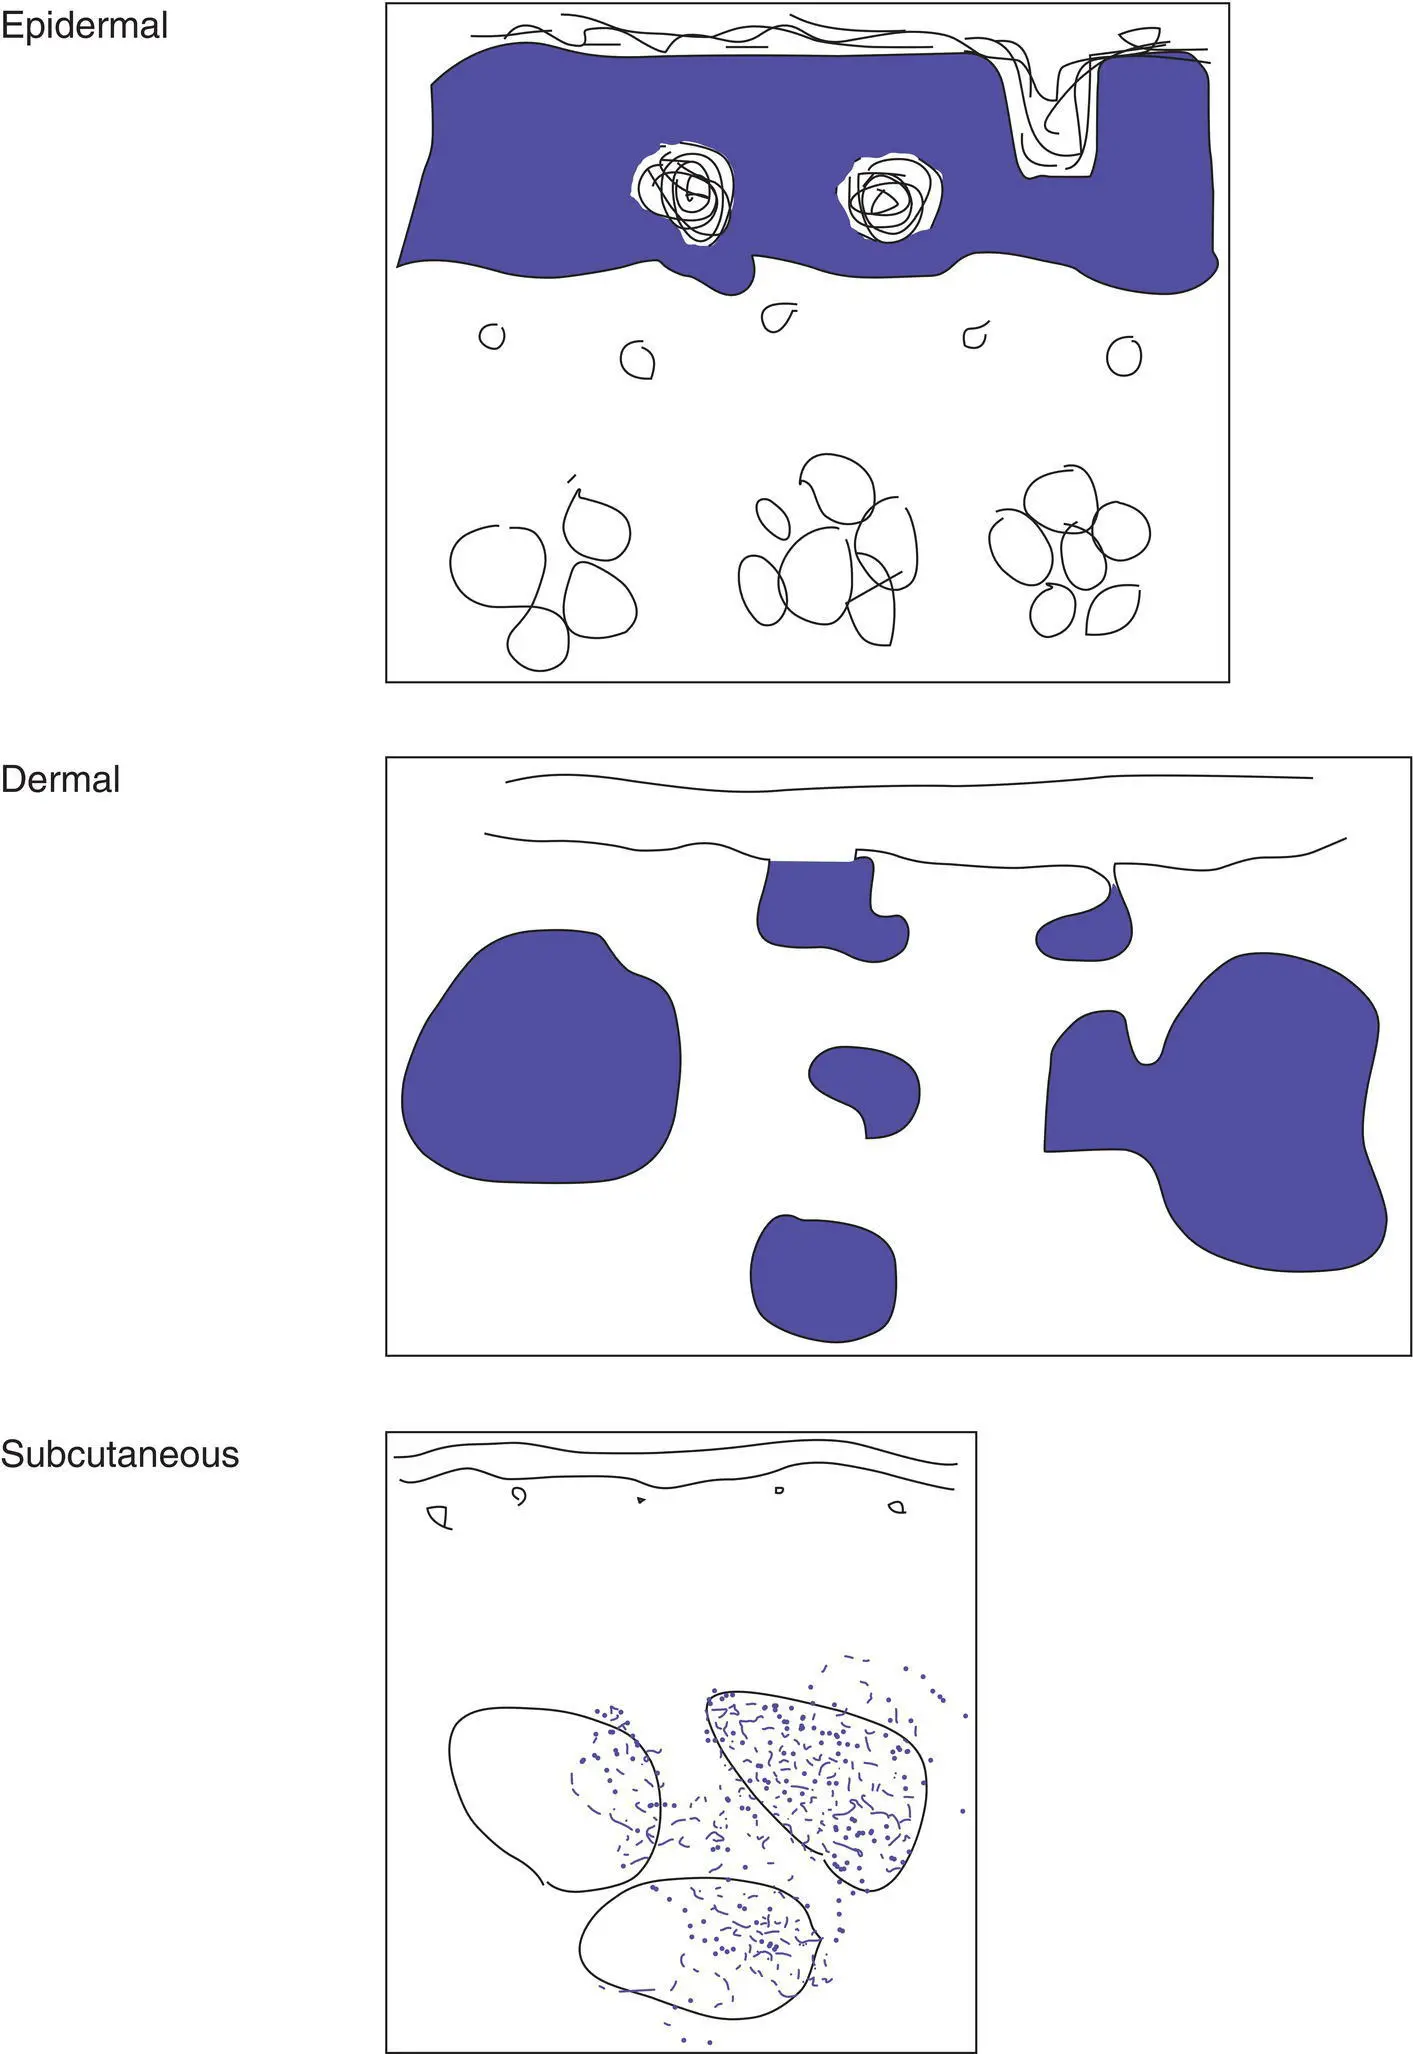

Figure 2(A)Location of the tumor

Important characteristics to consider for a tumor/growth include location (A), architecture (B), cell type (C), and benignancy versus malignancy (D). The eye can be trained to focus in on the blue areas (figure–ground separation; grouping)

Dermal tumors can have various architectural patterns

NoteBenign tumors are often symmetric with a pushing border, and malignant tumors may be asymmetric and infiltrative.